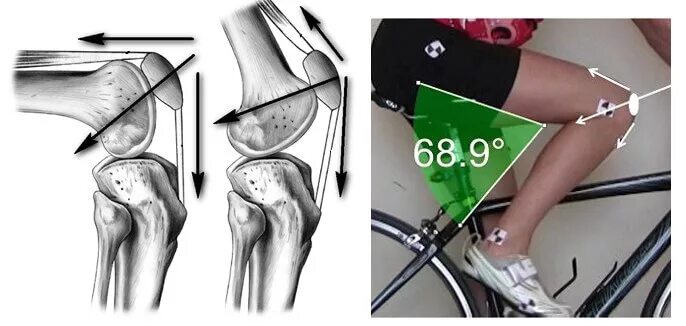

Строение мышц колена спереди. вид спереди коленного сустава симптомы. строение колена у человека спереди. коленный сустав правый вид спереди и сбоку.

Повреждение передней крестообразной связки. механизм травмы передней крестообразной связки коленного сустава. механизм разрыва крестообразных связок.

Задняя крестообразная связка коленного сустава анатомия. внутрисуставные связки коленного сустава. пкс анатомия строение коленного сустава. анатомия коленного сустава вид сбоку.

Строение мениска коленного сустава анатомия. мениски коленный сустав анатомия человека. латеральная коллатеральная связка коленного сустава. связки надколенника анатомия.